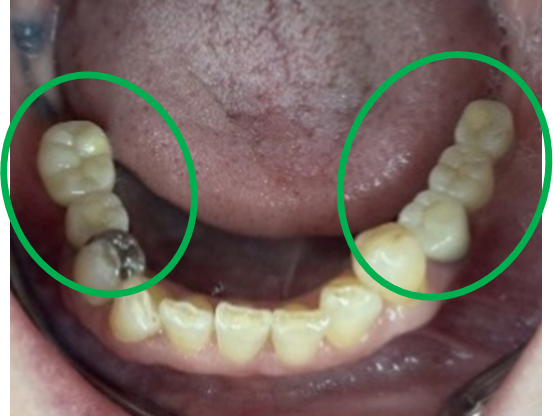

男性Kさん 60代(インプラント)

主訴

下の左右歯がないところに歯を入れたい。

治療内容

左右それぞれ3本歯がないところに2本ずつインプラントを埋入しました。

所感

上と下の歯の咬合接触がないすれ違い咬合です。上下義歯で対応するには最も難しいタイプの欠損状況です。治療開始前は、上下部分入れ歯が入っていましたが、入れ歯の安定が悪く、あちこちの歯茎に入れ歯が当たって痛く、満足に噛める状態ではありませんでした。上顎は、残ってる歯を活用するマグネット式総義歯を、下顎はインプラントを提案しました。上顎は、現在残っている歯の根管治療中です。上顎にマグネット式総義歯がはいれば、何でも食べられるようになります。

Before

▼初診時に使用していた部分入れ歯を装着したところ

▼インプラント埋入前